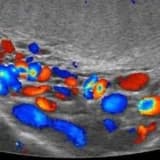

Skrotal varikosel renkli doppler ultrasonografi

TEŞHİS WHO varikoselin teşhis kriterlerini tanımlamıştır . Bu tanımlanan ve konsensusla kabul edilen kriterlere göre varikosel tanısı klinik muaye-neyle yapılır ve renkli doppler USG ile konfirme edilir. Antegrad ve retrograd embolizasyon ve sklerotera-piyle tedavi yapılan merkezlerde radyolojik görüntüleme ile teşhis konfirme edilir. Klinik muayeneyle tanı konulamayan sadece yardımcı tanı yöntemler ile tesbit edilen vari-koseller subklinik varikosel olarak adlandırılmaktadır.